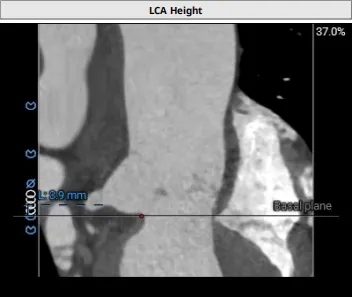

冠脉风险评估

Left Coronary 3.9mm

Right Coronary 17.1mm

左冠开口较低,,结合瓦氏窦大小,预估冠脉风险相对较低